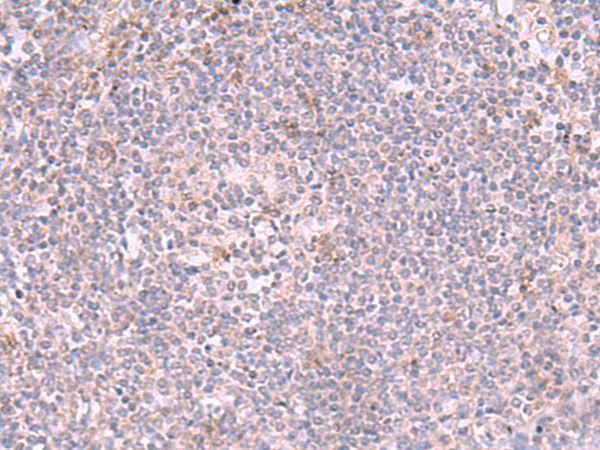

IHC positive control:

Human tonsil and Human lung cancer

IHC Recommend dilution:

50-300